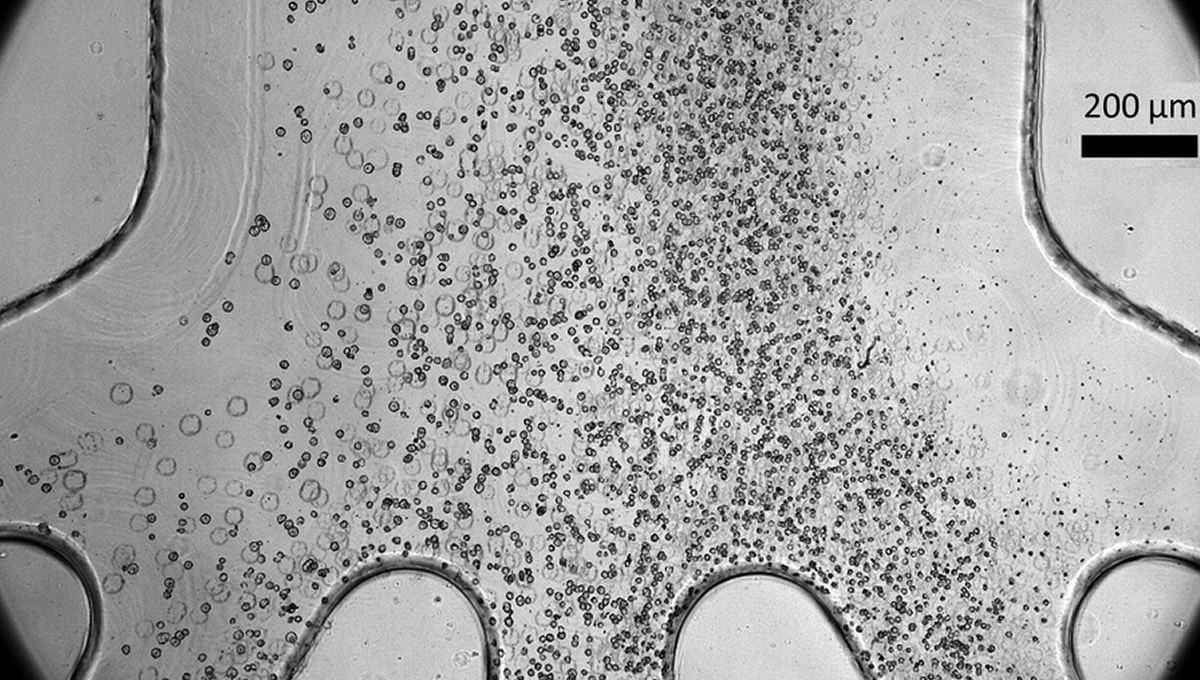

Concretamente han desarrollado un clasificador de células microfluídicas capaz de eliminar aproximadamente la mitad de las células indiferenciadas en un lote, sin causar ningún daño a las células progenitoras completamente formadas. Se trata de un dispositivo de alto rendimiento, que no requiere productos químicos especiales, que puede llegar a clasificar más de 3 millones de células por minuto y que además es fácil de implementar a gran escala por su bajo coste de producción.

Los investigadores descubrieron, gracias a su trabajo, que las células madre pluripotentes suelen ser más grandes que los progenitores derivados de ellas. Se plantea la hipótesis de que antes de que una célula madre pluripotente se diferencie, su núcleo contiene una gran cantidad de genes que no han sido desactivados o suprimidos. A medida que se diferencia para una función específica, la célula suprime muchos genes que ya no necesitará, lo que reduce significativamente el tamaño del núcleo. Entonces el dispositivo de microfluidos aprovecha esta diferencia de tamaño para clasificar las células.